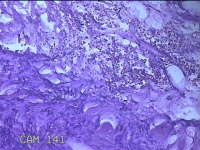

右侧前臂结节

性别

女

年龄

38岁

临床诊断

皮下结节

一般病史

发现右侧前臂结节1年余。

标本名称

大体所见

灰白粉红色带皮肤样组织0.8x0.7x0.3cm一块,表面带梭形皮肤0.8x0.7cm,皮下见结节0.8x0.5x0.3cm一个,切开结节呈实性,切面灰白粉红色,质软。